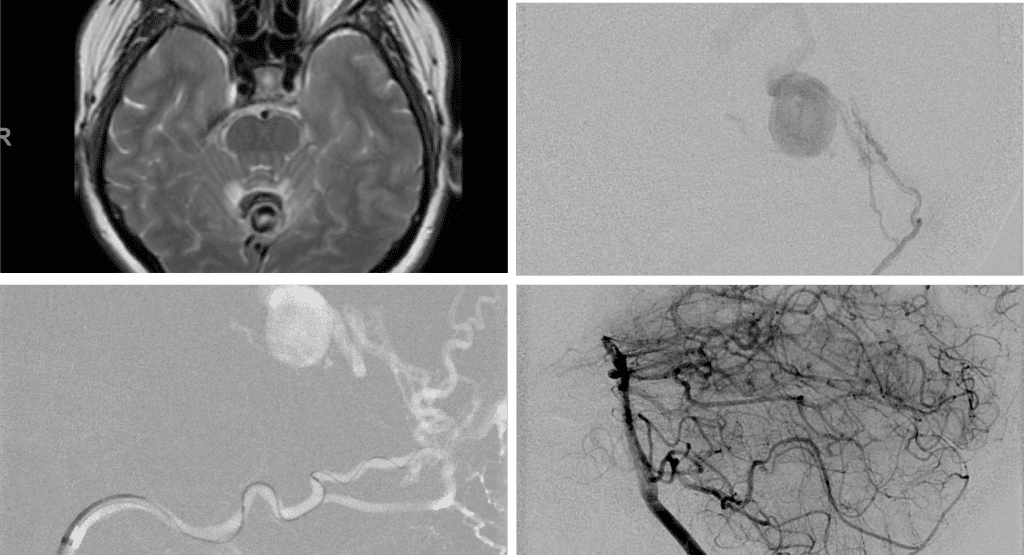

Over the 12 to 18 months, she continued to remain event-free and maintain her active independent lifestyle. Delayed angiography over that period confirmed complete obliteration of the Left ECA and Vertebral Artery shunts with near complete obliteration of the Right ECA shunts (Figure 7).

Figure 7. 12 mos follow-up angiograms confirm complete obliteration of the left ECA and Vertebral Supply to the AVM, with a small late-filling component from the right Occipital artery that is markedly Reduced in size and flow (top row). Near complete resolution of the aneurysm and hematoma Is observed on 16 mos post Gamma Knife MRI (bottom row).